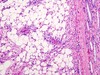

Globoid cells in Krabbe disease (AR and a galcotocerebrosidase deficiency)